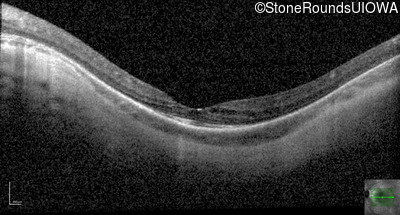

Optical Coherence Tomography - Left - 10/25 -1

Exemplar / OCT Stack

OCT Stack